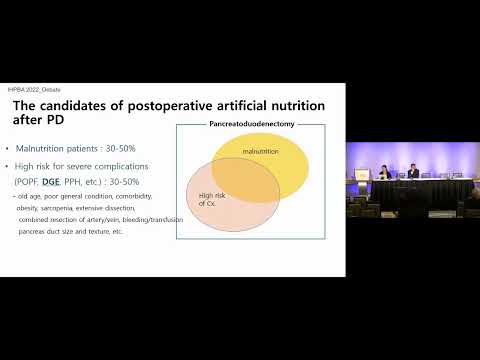

DEB08: Routine Enteral Tube Feeding vs Oral Feeding (Nutrition after Pancreatoduodenectomy)

Debate 08: Routine Enteral Tube Feeding vs Oral Feeding (Nutrition after Pancreatoduodenectomy)